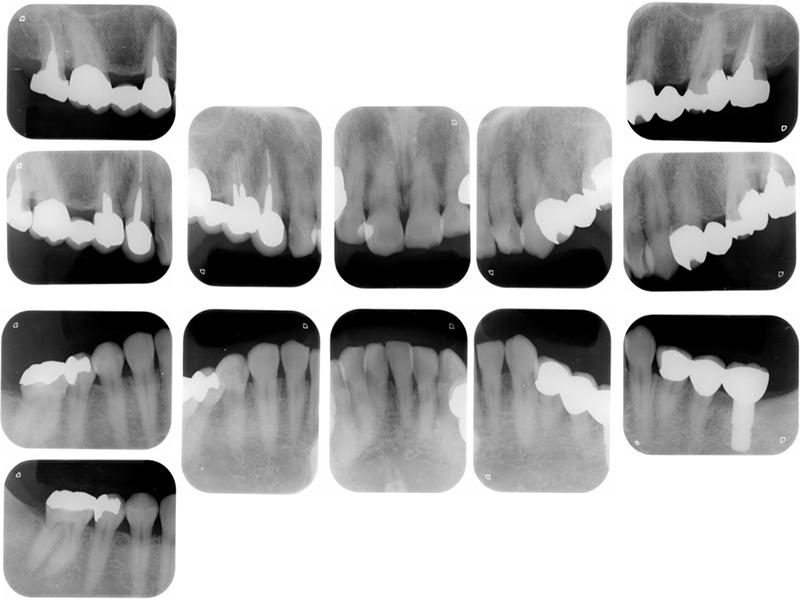

▼ ケース5 下顎前歯部叢生症例

初診時X線写真

治療終了時